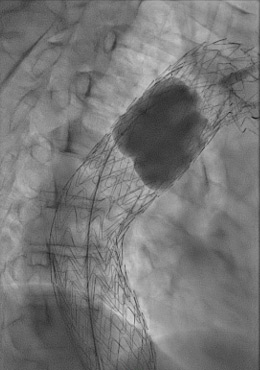

Staged deployment of the tapered TAG® Conformable with precise control of the distal landing zone.

Ballooning under controlled hypotension with a Tri-Lobe balloon.